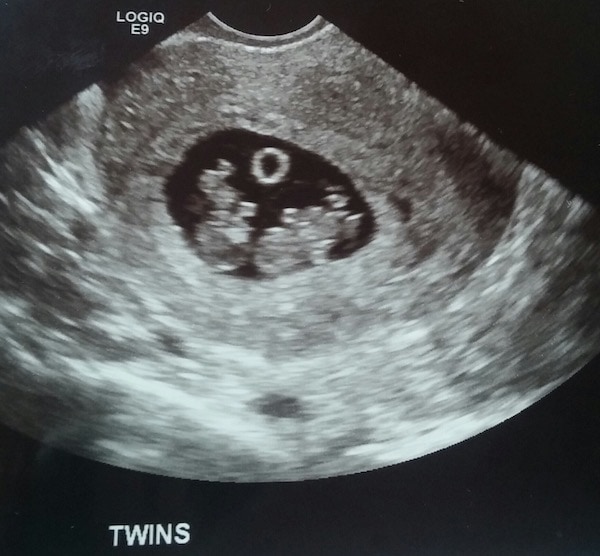

The first sonogram can take place anywhere in the first 6-12 weeks of your pregnancy, depending on your doctors’ preferences and your individual situation. Your doctor uses this scan to listen to your babies’ heartrates—yes! They’re already there—and determine your estimated due date. It’s possible, but not always a definite, that twins can be confirmed at this early stage. You’ll want to arrive at this first appointment armed with a family history from both you and your partner and any questions you have for your provider regarding your pregnancy.